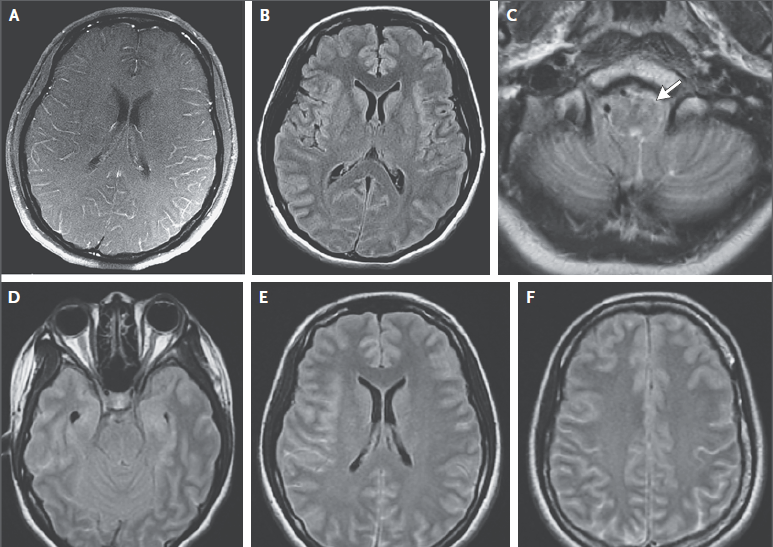

Dos semanas después de la aparición de los síntomas, el entumecimiento de la hemicara se resolvió pero desarrolló ptosis del párpado superior izquierdo junto con la visión doble caracterizada por una imagen que aparecía en diagonal sobre otra. La paciente consultó a otro hospital, donde se hizo una TC y una angio-TC de cabeza y cuello que reveló engrosamiento de la mucosa de los senos etmoidales y seno esfenoidal izquierdo, así como los niveles hidroaéreos en los senos maxilares bilateralmente. Un recuento sanguíneo completo, recuento diferencial de glóbulos blancos, y panel metabólico fueron normales, y una prueba de embarazo fue negativa. Se administró un curso de 2 semanas de un agente antibiótico no especificado. Varios días después, una resonancia magnética (RMN) de cráneo, después de la administración de gadolinio, al parecer reveló cambios consistentes con sinusitis, pero lo demás era normal. La agudeza visual era de 20/20 en ambos ojos, y un oftalmólogo le recetó un parche en el ojo para tratar la diplopía. Análisis de líquido cefalorraquídeo que se obtuvo por punción lumbar (incluyendo las pruebas de ácido nucleico del virus del herpes simple) y hemocultivos fueron negativos según los informes.

Dos semanas antes de la internación, comenzó con dolor periorbitario en el lado medial izquierdo, sin presión, dolor de cabeza, o visión doble. Una semana más tarde, repitió diplopia, con desviación anormal asociada del ojo izquierdo. Los resultados de estudios de potenciales evocados visuales eran no diagnósticos. En el ojo izquierdo, la agudeza visual se redujo y la discriminación para color era anormal. Tres días antes de su ingreso, la paciente tuvo náuseas y vómitos, junto con vértigo que dio lugar a caída en su cuarto de baño. La diplopía persistió, y el dolor periorbitario izquierdo era de 5 en una escala de 0 a 10 (con 10 indicando el dolor más severo). La noche antes de la internación se repitió la RMN en el segundo hospital.7

RMN de cráneo mostró tejido blando anormal a lo largo de las paredes anterior y lateral del seno esfenoidal izquierdo, en el vértice de la órbita izquierda extendiéndose posteriormente en el seno cavernoso izquierdo. Este tejido blando era de densidad intermedia tanto en una imagen potenciada en T2 (Figura A) Y una imagen potenciada en T1 con contraste (Figura 1B). Una imagen de RMN con contraste, coronal (Figura 1C) mostró aumento anormal en la unión del seno cavernoso y la cavum de Meckel en el lado izquierdo, con realce de tejido que se extendía a la parte interna del foramen oval.

RMN DE ÓRBITAS REALIZADA EN OTRO HOSPITAL. Una imagen en T2 (Panel A)y una T1 con contraste (Panel B) muestra tejido de densidad intermedia tapizando el seno esfenoidal y afectando el vértice de la órbita izquierda y el seno cavernoso (flechas). Un corte coronal en T1 (Panel C) muestra realce de partes blandas extendiéndose inferiormente al foramen oval. Una TC de órbita (Panel D) muestra que el hueso entre el seno esfenoidal y el vértice de la órbita están relativamente intactos a pesar de la presencia de tejido con densidad de partes blandas anormal a ambos lados (flecha).